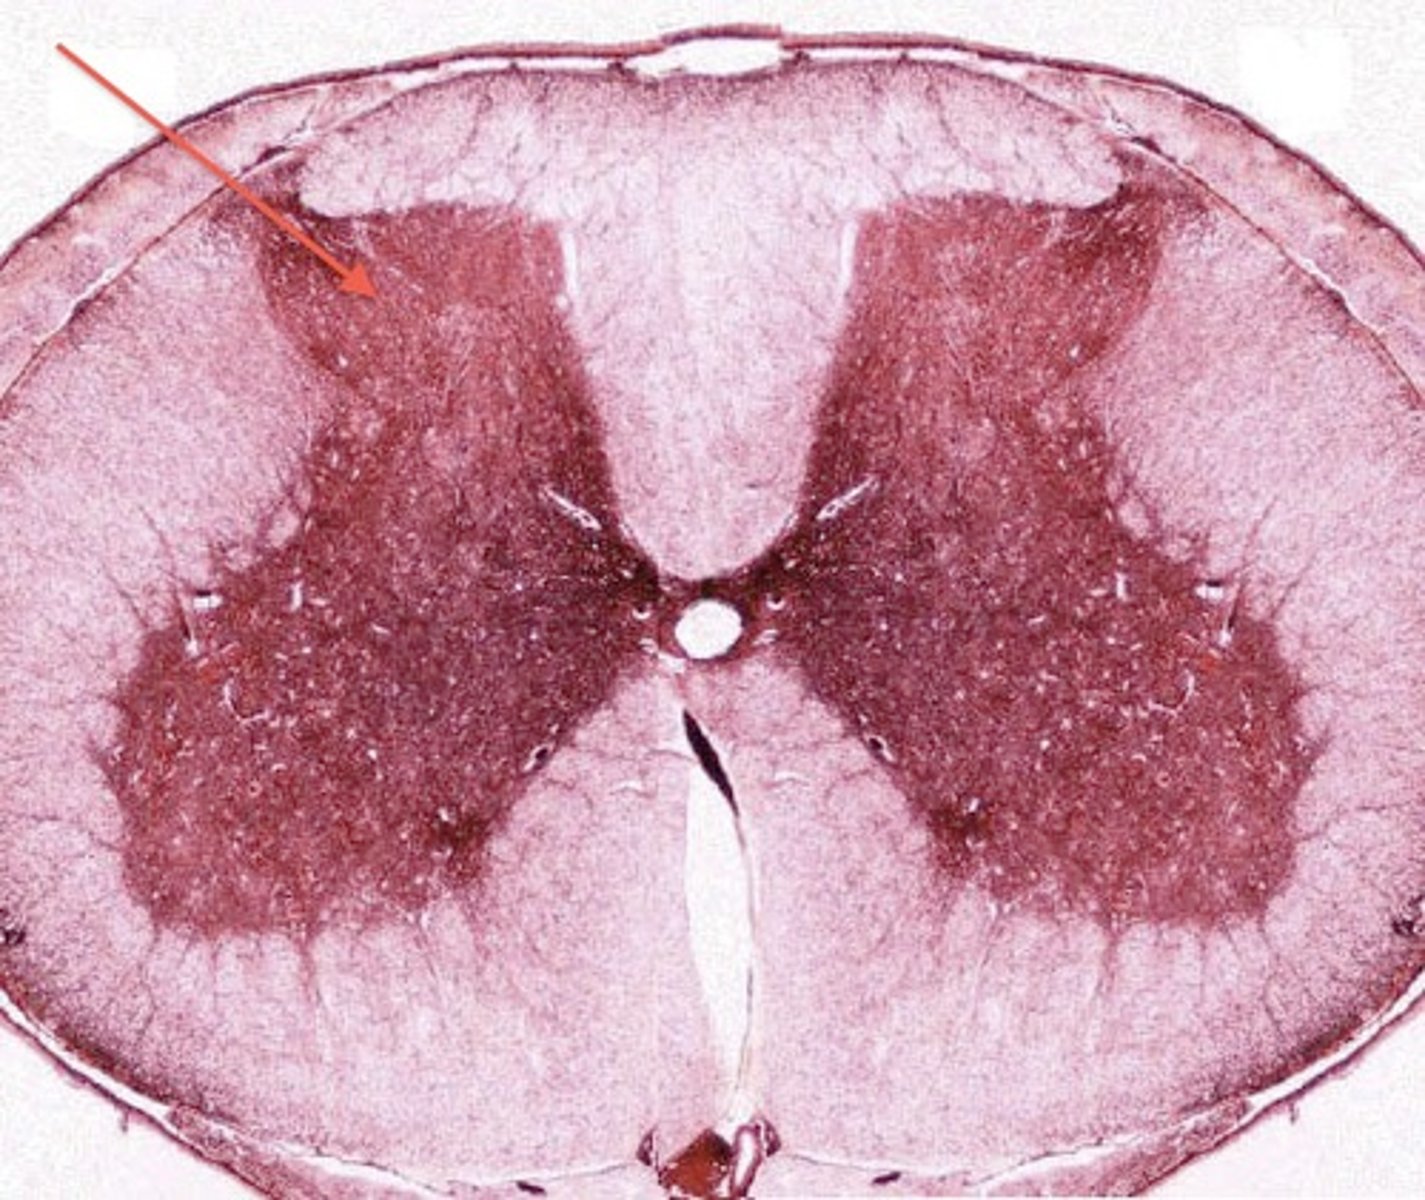

grey matter

knowt flashcard image